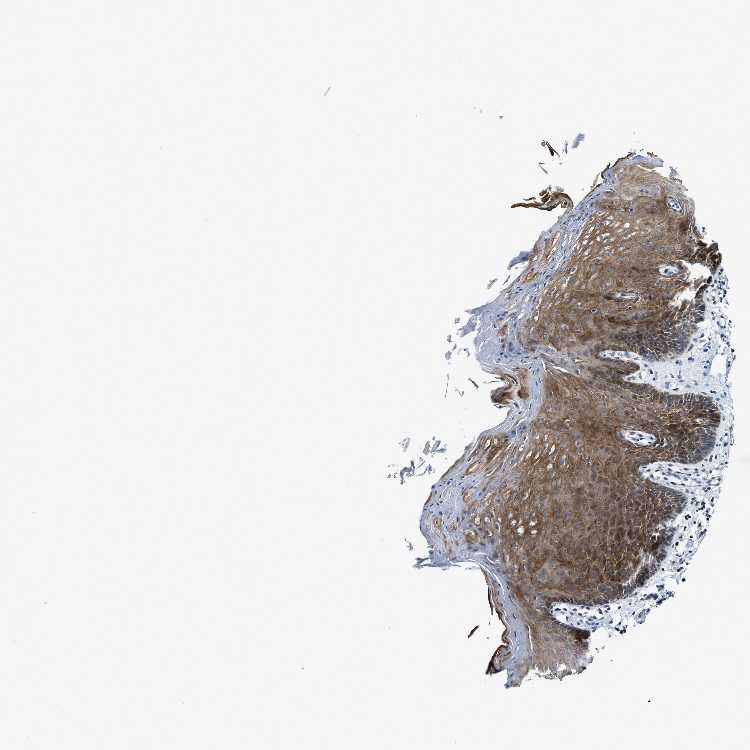

ORAL MUCOSA - Antibody stainingi

Antibody staining in the annotated cell types in the current human tissue is reported as not detected, low, medium, or high, based on conventional immunohistochemistry profiling in selected tissues. This score is based on the combination of the staining intensity and fraction of stained cells.

Each image is clickable and will lead to virtual microscopy that enables deeper exploration of all samples and also displays staining intensity scores, fraction scores and subcellular localization as well as patient and tissue information for each sample.

Antibody HPA017377Antibody CAB012422

Squamous epithelial cells MediumNot detected